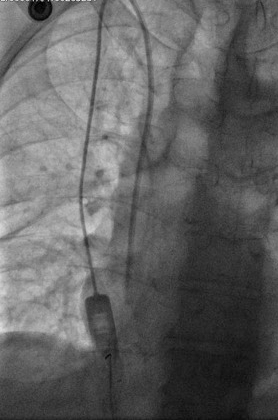

Percutaneous transhepatic cholangiography. Cystic dilatation of intrahepatic biliary duct with mucinous content (Courtesy Dr. V. Penopoulos)